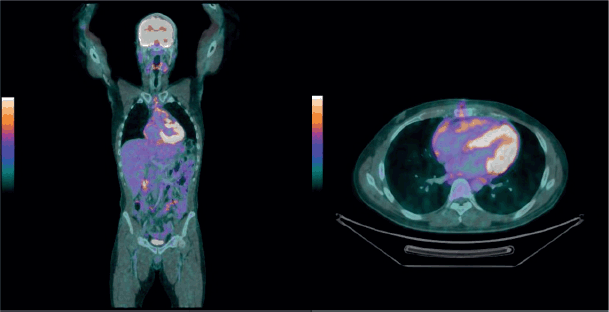

Additional tests, such as positron emission tomography/computed tomography (PET-CT), revealed global cardiomegaly, multiple nodular areas of pericardial thickening, a solid lesion near the aortic root (62 × 27 mm) with increased metabolic activity (SUVmax 12.0) and involved lymph nodes (Figure 1).

Figure 1. FDG PET positive for a solid lesion in the superior pericardial recess, extending to the myocardium (anterior wall of the left ventricle), as well as multiple solid nodules diffusely distributed in the pericardium and mediastinal lymph nodes with hypermetabolism.